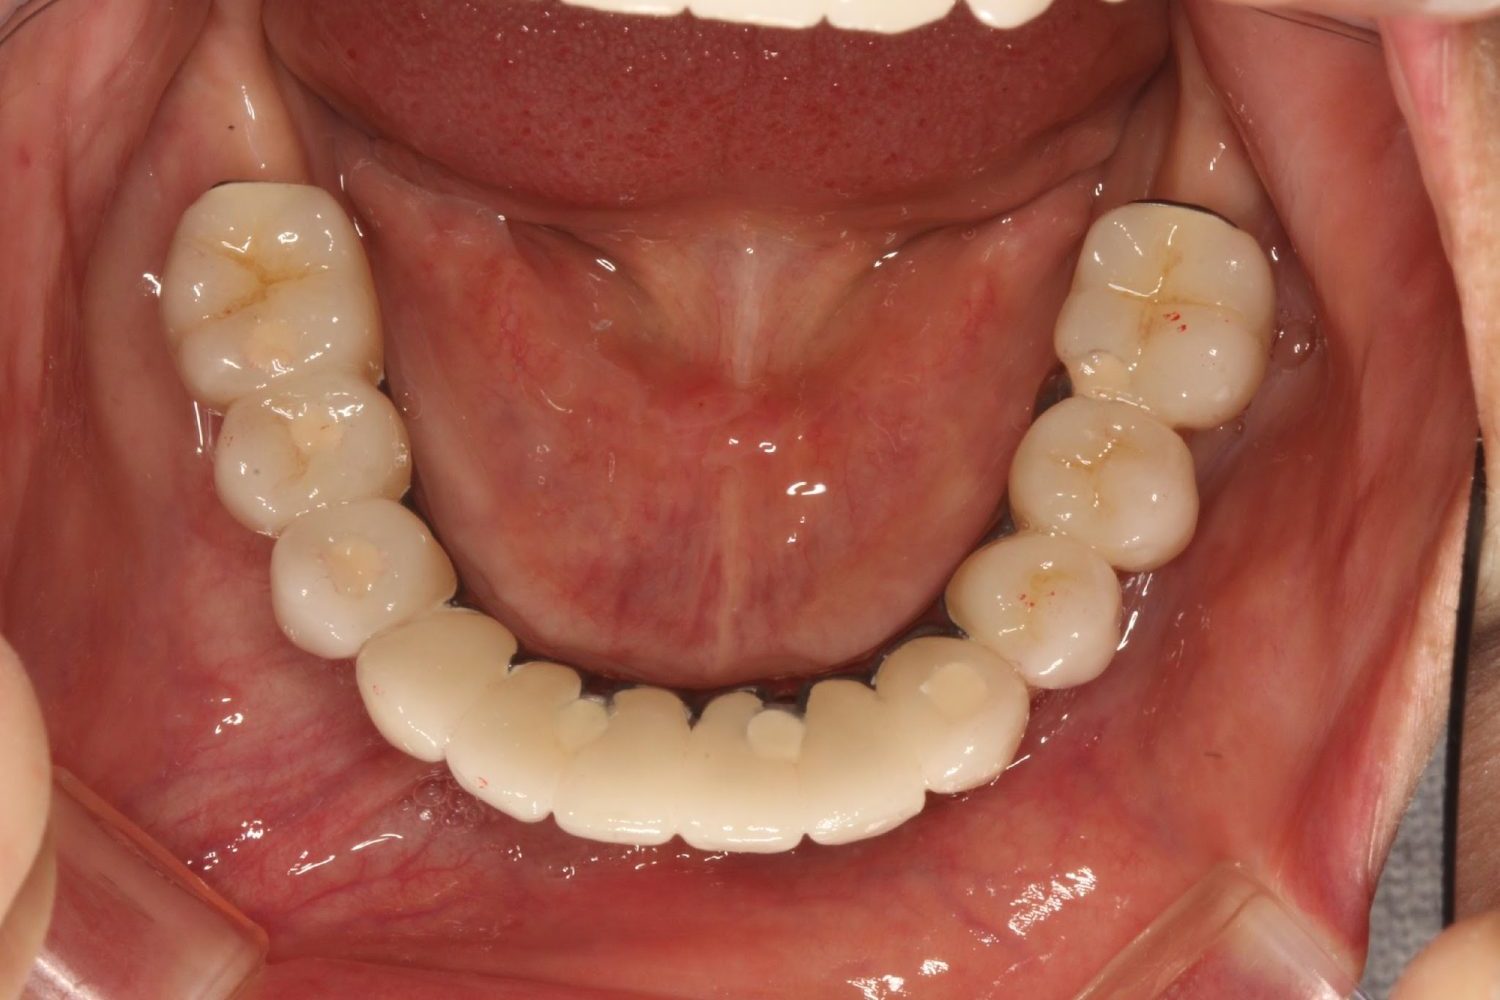

インプラント治療の症例紹介⑤

Before

After

主訴

歯肉腫脹、咬めるようにしたい

治療内容

重度歯周病により全ての残存歯保存不可能な状態。上下顎ボーンアンカードブリッジによる咬合再構成。

治療費

12,621,400円(税込)

治療期間

22ヶ月

通院回数

28回

想定されたリスク

※上部構造の形態が複雑になるため清掃が難しくなる、インプラント周囲炎の恐れがありました。

濱 仁隆先生

浜歯科

上顎8本下顎7本のインプラント体埋入によるボーンアンカードブリッジ。